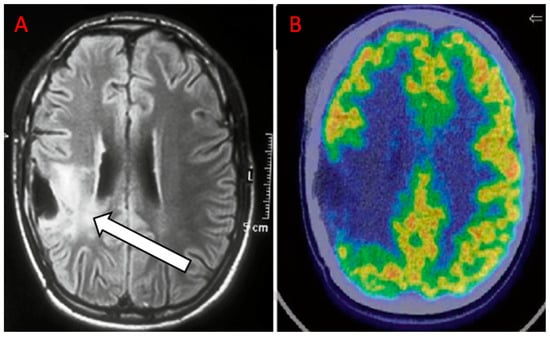

| Jena et al. [35] | 2017 | R | 35 | II = 9 III = 13 IV = 19 | PET/MR | DWI, PWI, MRS | PET provides complementary information to MRI. The AUC obtained combining MRI metrics (rCBV, mean ADC, Cho/Cr) and the PET parameter (mean T/N) was higher (0.935 ± 0.046) than the curve that resulted only from the three MRI parameters (0.913 ± 0.053). |